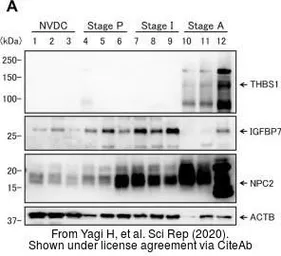

The data was published in the journal Sci Rep in 2020.PMID: 32286426